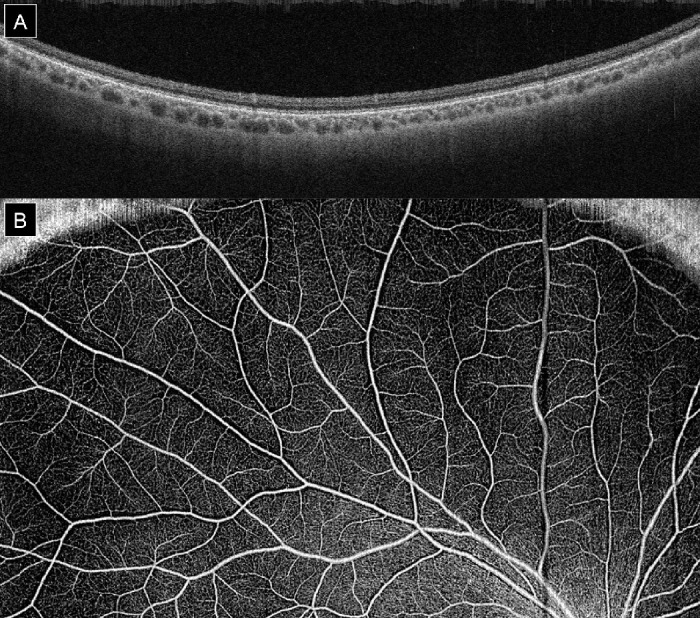

Methods: Widefield optical coherence tomography angiography and enhanced depth imaging (EDI)-OCT images of the retina were used to acquire digital images of the choroidal and retinal vasculature in 32 eyes with axial myopia and 14 emmetropic control population eyes. Retinal vessel density was calculated using Otsu's method and used for quantitative comparison of retinal vascular architecture and perfusion ability with increasing retinal surface area. The choroidal vascularity index was also calculated from skeletonized 15 × 9 mm swept-source EDI-OCT images. Correlations were sought between increasing myopia and the retinal vessel density and choroidal vascularity index.

Results: Increased axial myopia was negatively correlated with retinal vessel density (r2 = 0.35, P < 0.001) and positively correlated with choroidal vascularity index (r2 = 0.31, P < 0.001).

Conclusions: Increased retinal surface area in myopia results in decreased retinal vascular surface coverage. The inadequacy of retinal vascular coverage is compensated for by increased choroidal vascularity index in high myopes. This adaptive change may enable oxygen diffusion from choroidal vessels to the relatively thinner retina, thereby supplementing the oxygen needs of the inner retinal neurons.